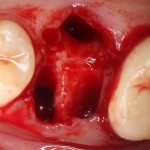

Очень аккуратно удалили зуб. Убрали из лунки все грануляции. В область верхушки корня зуба — Neocones, остальная часть альвеолы — Bioss Collagen. Сама лунка запечатывается Mucograft Seal:

Который подшивается к ее краям:

Пациенту даются обычные рекомендации после удаления зуба. Контрольный осмотр — через день:

И вот тут я подумал, что пришла беда. Решил, что Mucograft Seal развалился (пациент курит), что с дня на день нужно ждать альвеолит.

Но оказалось иначе. Никаких беспокойств, никаких проблем, никакого дискомфорта. Сняли швы через неделю, с пациентом расстались на полтора месяца.